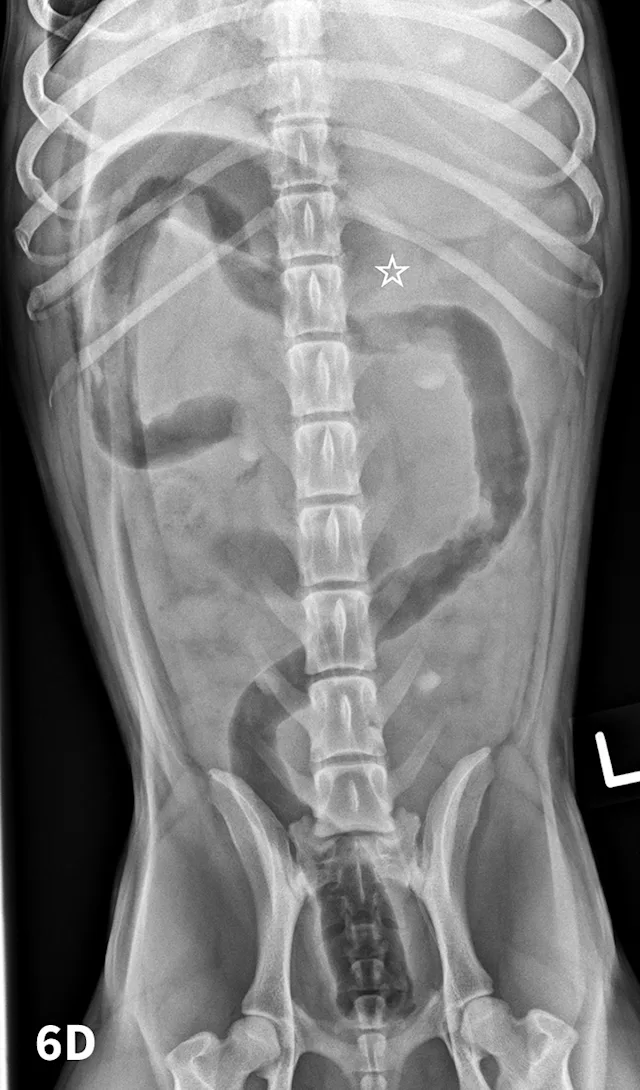

In cases of suspected FBs, this technique can be helpful to differentiate dilated small intestinal loops from colon or determine whether mottled mineralized material is in the colon or small intestinal tract. After initial survey radiographs are taken (Figures 6A and 6B), the animal is placed in lateral recumbency. Air is instilled into the rectum and colon using a large lubricated syringe or rubber catheter; approximately 10 to 12 mL/kg of air is needed for moderate distention of the colon.6,7 Standard lateral and ventrodorsal radiographs are then taken (Figures 6C and 6D). In most animals, it is desirable to fill the colon to the cecum. Partial filling of the distal jejunum and ileum may occur and is normal.

Left lateral (A) and VD (B) survey radiographs of a 4-year-old pit bull terrier with a 3-day history of vomiting, diarrhea, and anorexia. A dilated loop of bowel is present within the midabdomen (star) caudal to the stomach, which could represent large or small bowel.